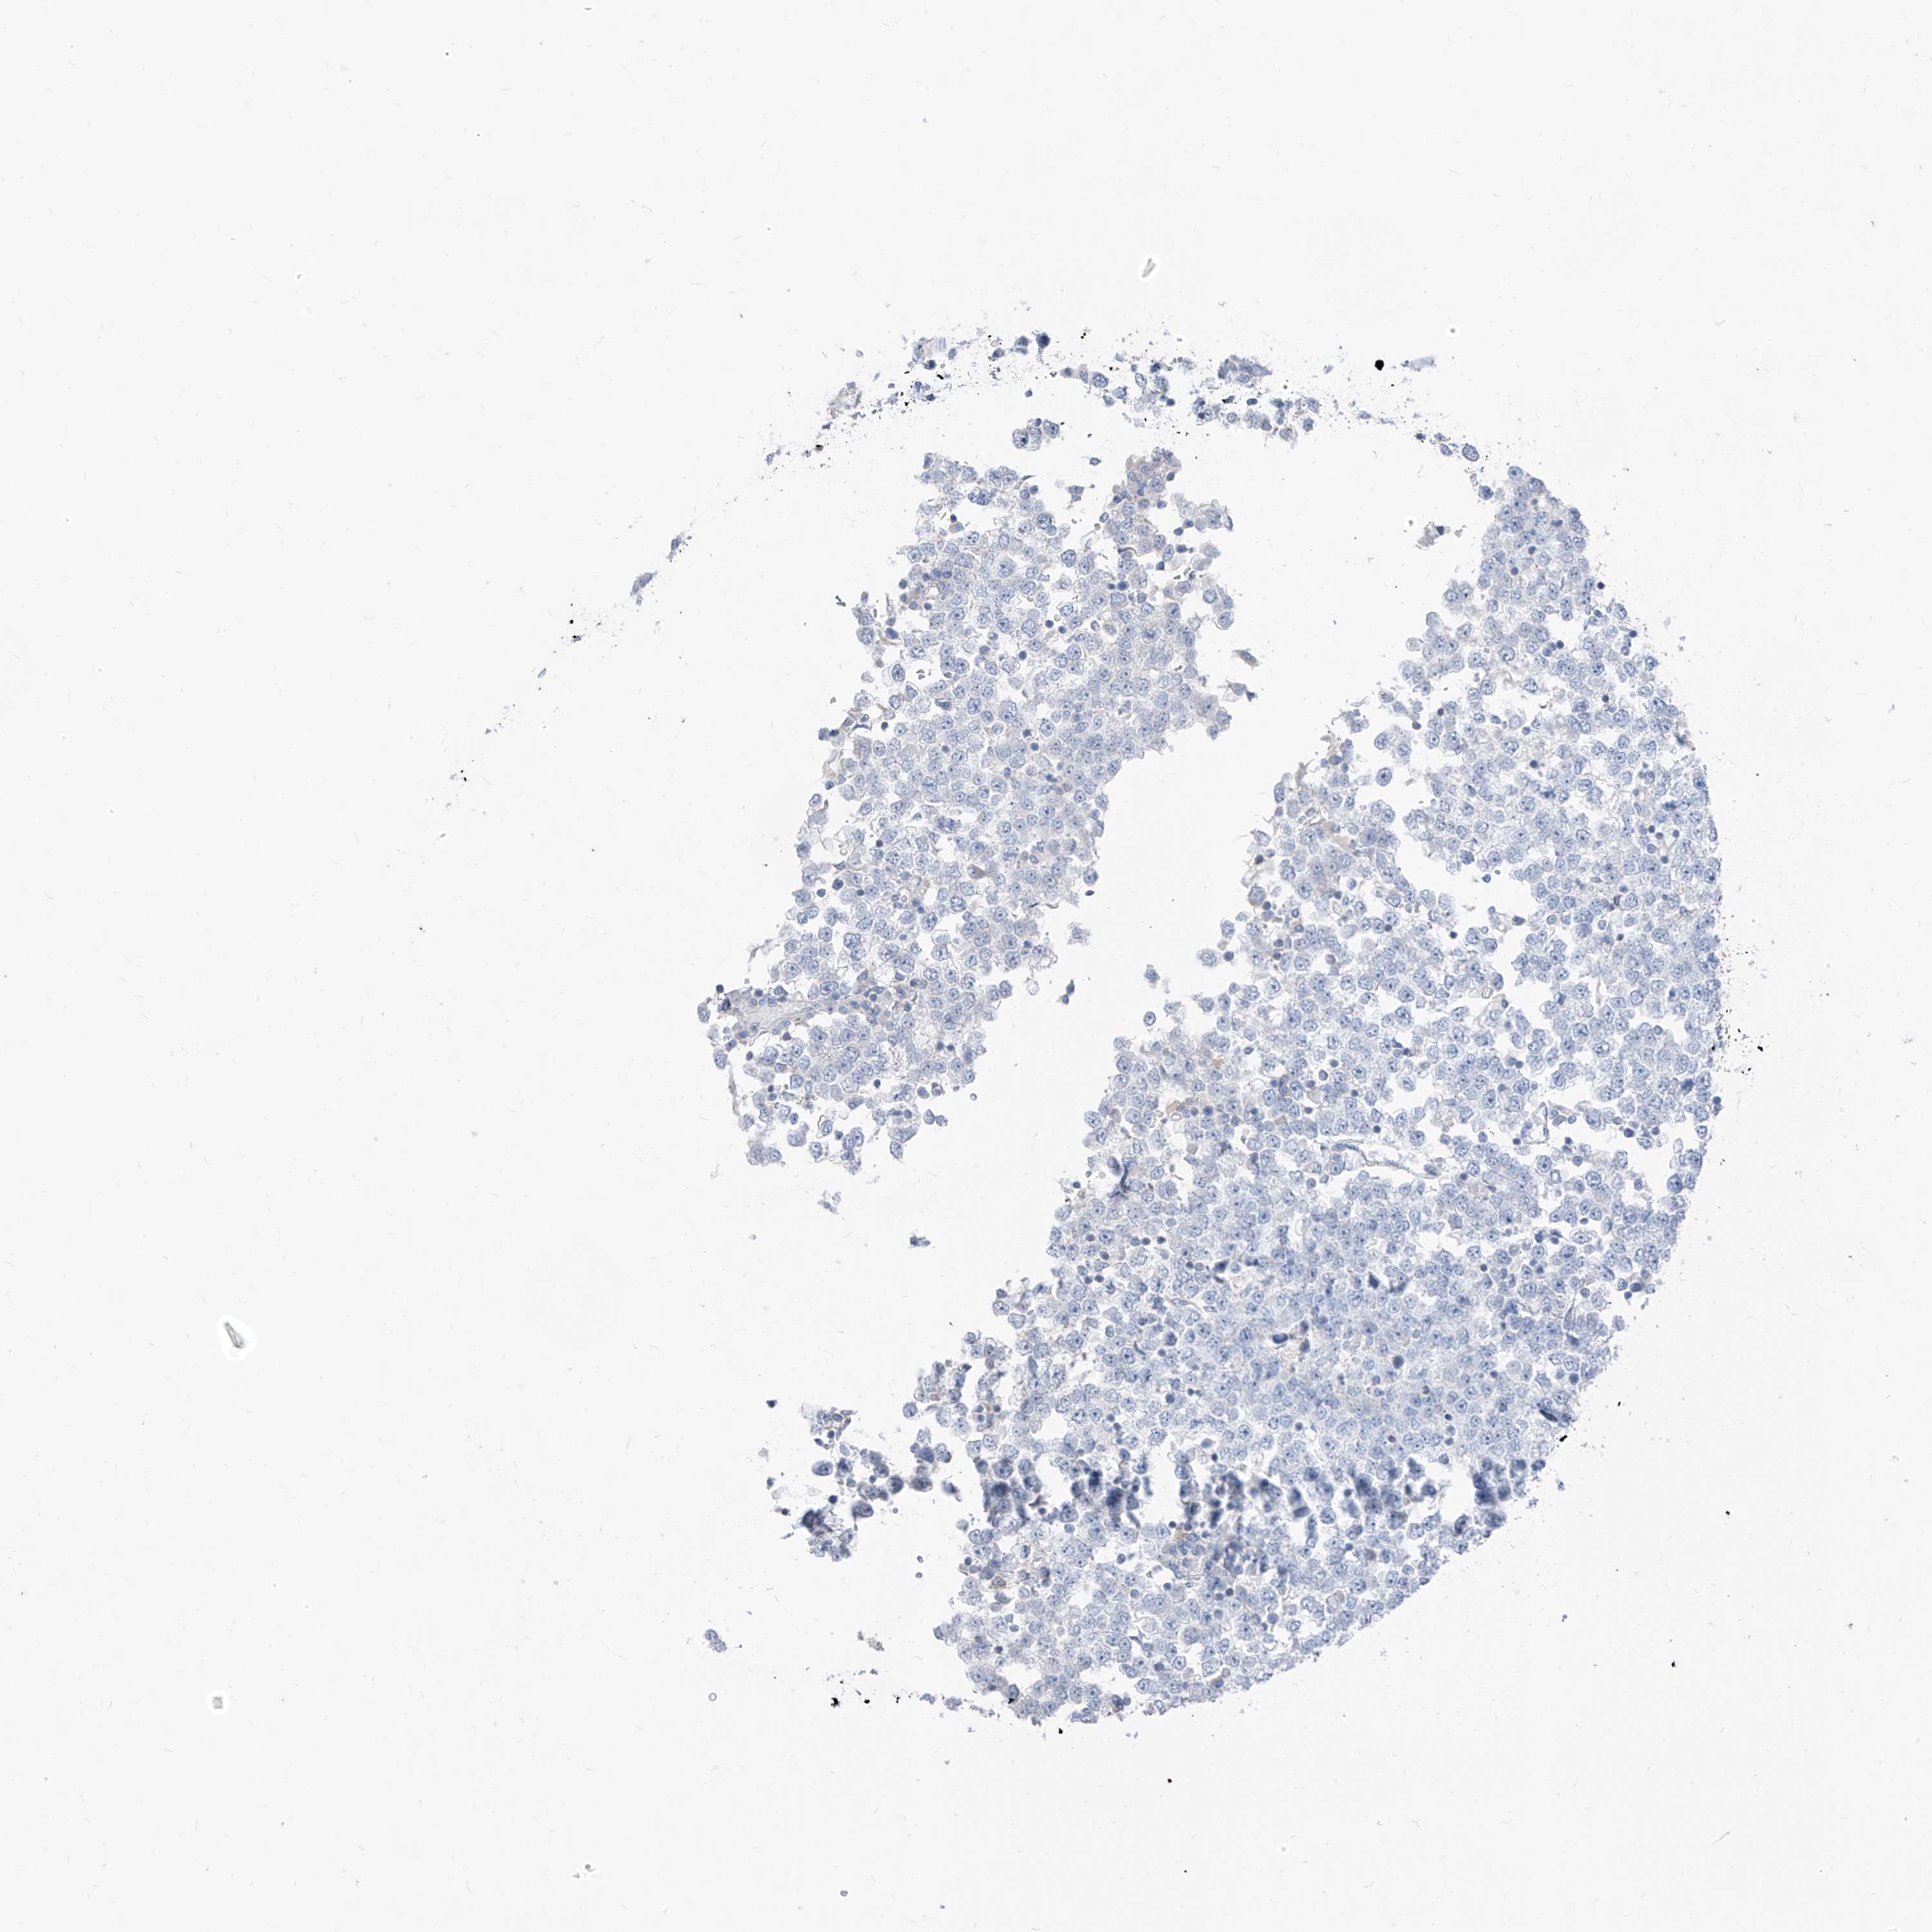

TESTIS CANCER - Protein expressioni

A mouse-over function shows sample information and annotation data. Click on an image to view it in a full screen mode. Samples can be filtered based on level of antibody staining by selecting one or several of the following categories: high, medium, low and not detected. The assay and annotation is described here.

Note that samples used for immunohistochemistry by the Human Protein Atlas do not correspond to samples in the TCGA dataset.

Antibody HPA030763

Carcinoma, Embryonal, NOS

Seminoma, NOS

Urothelial carcinoma, High grade